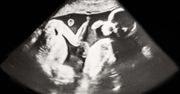

Duńska influencerka Michella Meier-Morsi, którą na Instagramie obserwuje prawie 300 tys. osób, pochwaliła się w sieci zdjęciami swojego ciążowego brzucha oraz tym, jak wygląda teraz, po urodzeniu trojaczków. Wywołała też spore poruszenie w sieci przez to, co powiedziała na kilka dni przed rozwiązaniem.